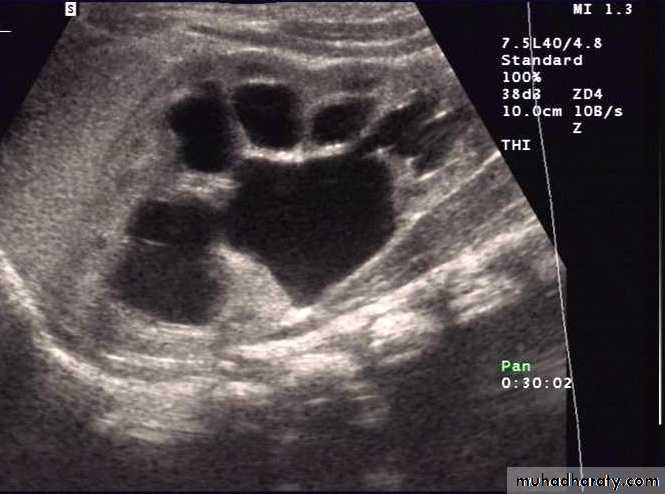

Multicystic dysplastic kidney1.hypoechoic cysts of variable sizes and shapes,2.interfaces between cysts, 3.absence of an identifiable renal sinus, 4.lack of communication between cysts on sonograms,5. minimal surrounding parenchyma